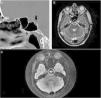

CSF rhinorrhea is a rare presenting symptom of a clival chordoma as these tumors do not tend to show dural invasion as a histological feature. Here we discuss the case of a 61 years old female with spontaneous rhinorrhea secondary to a clival chordoma, and the value of some specific MRI sequences in accurate identification of a tumor with such atypical presentation, enabling the surgeon to plan accordingly.